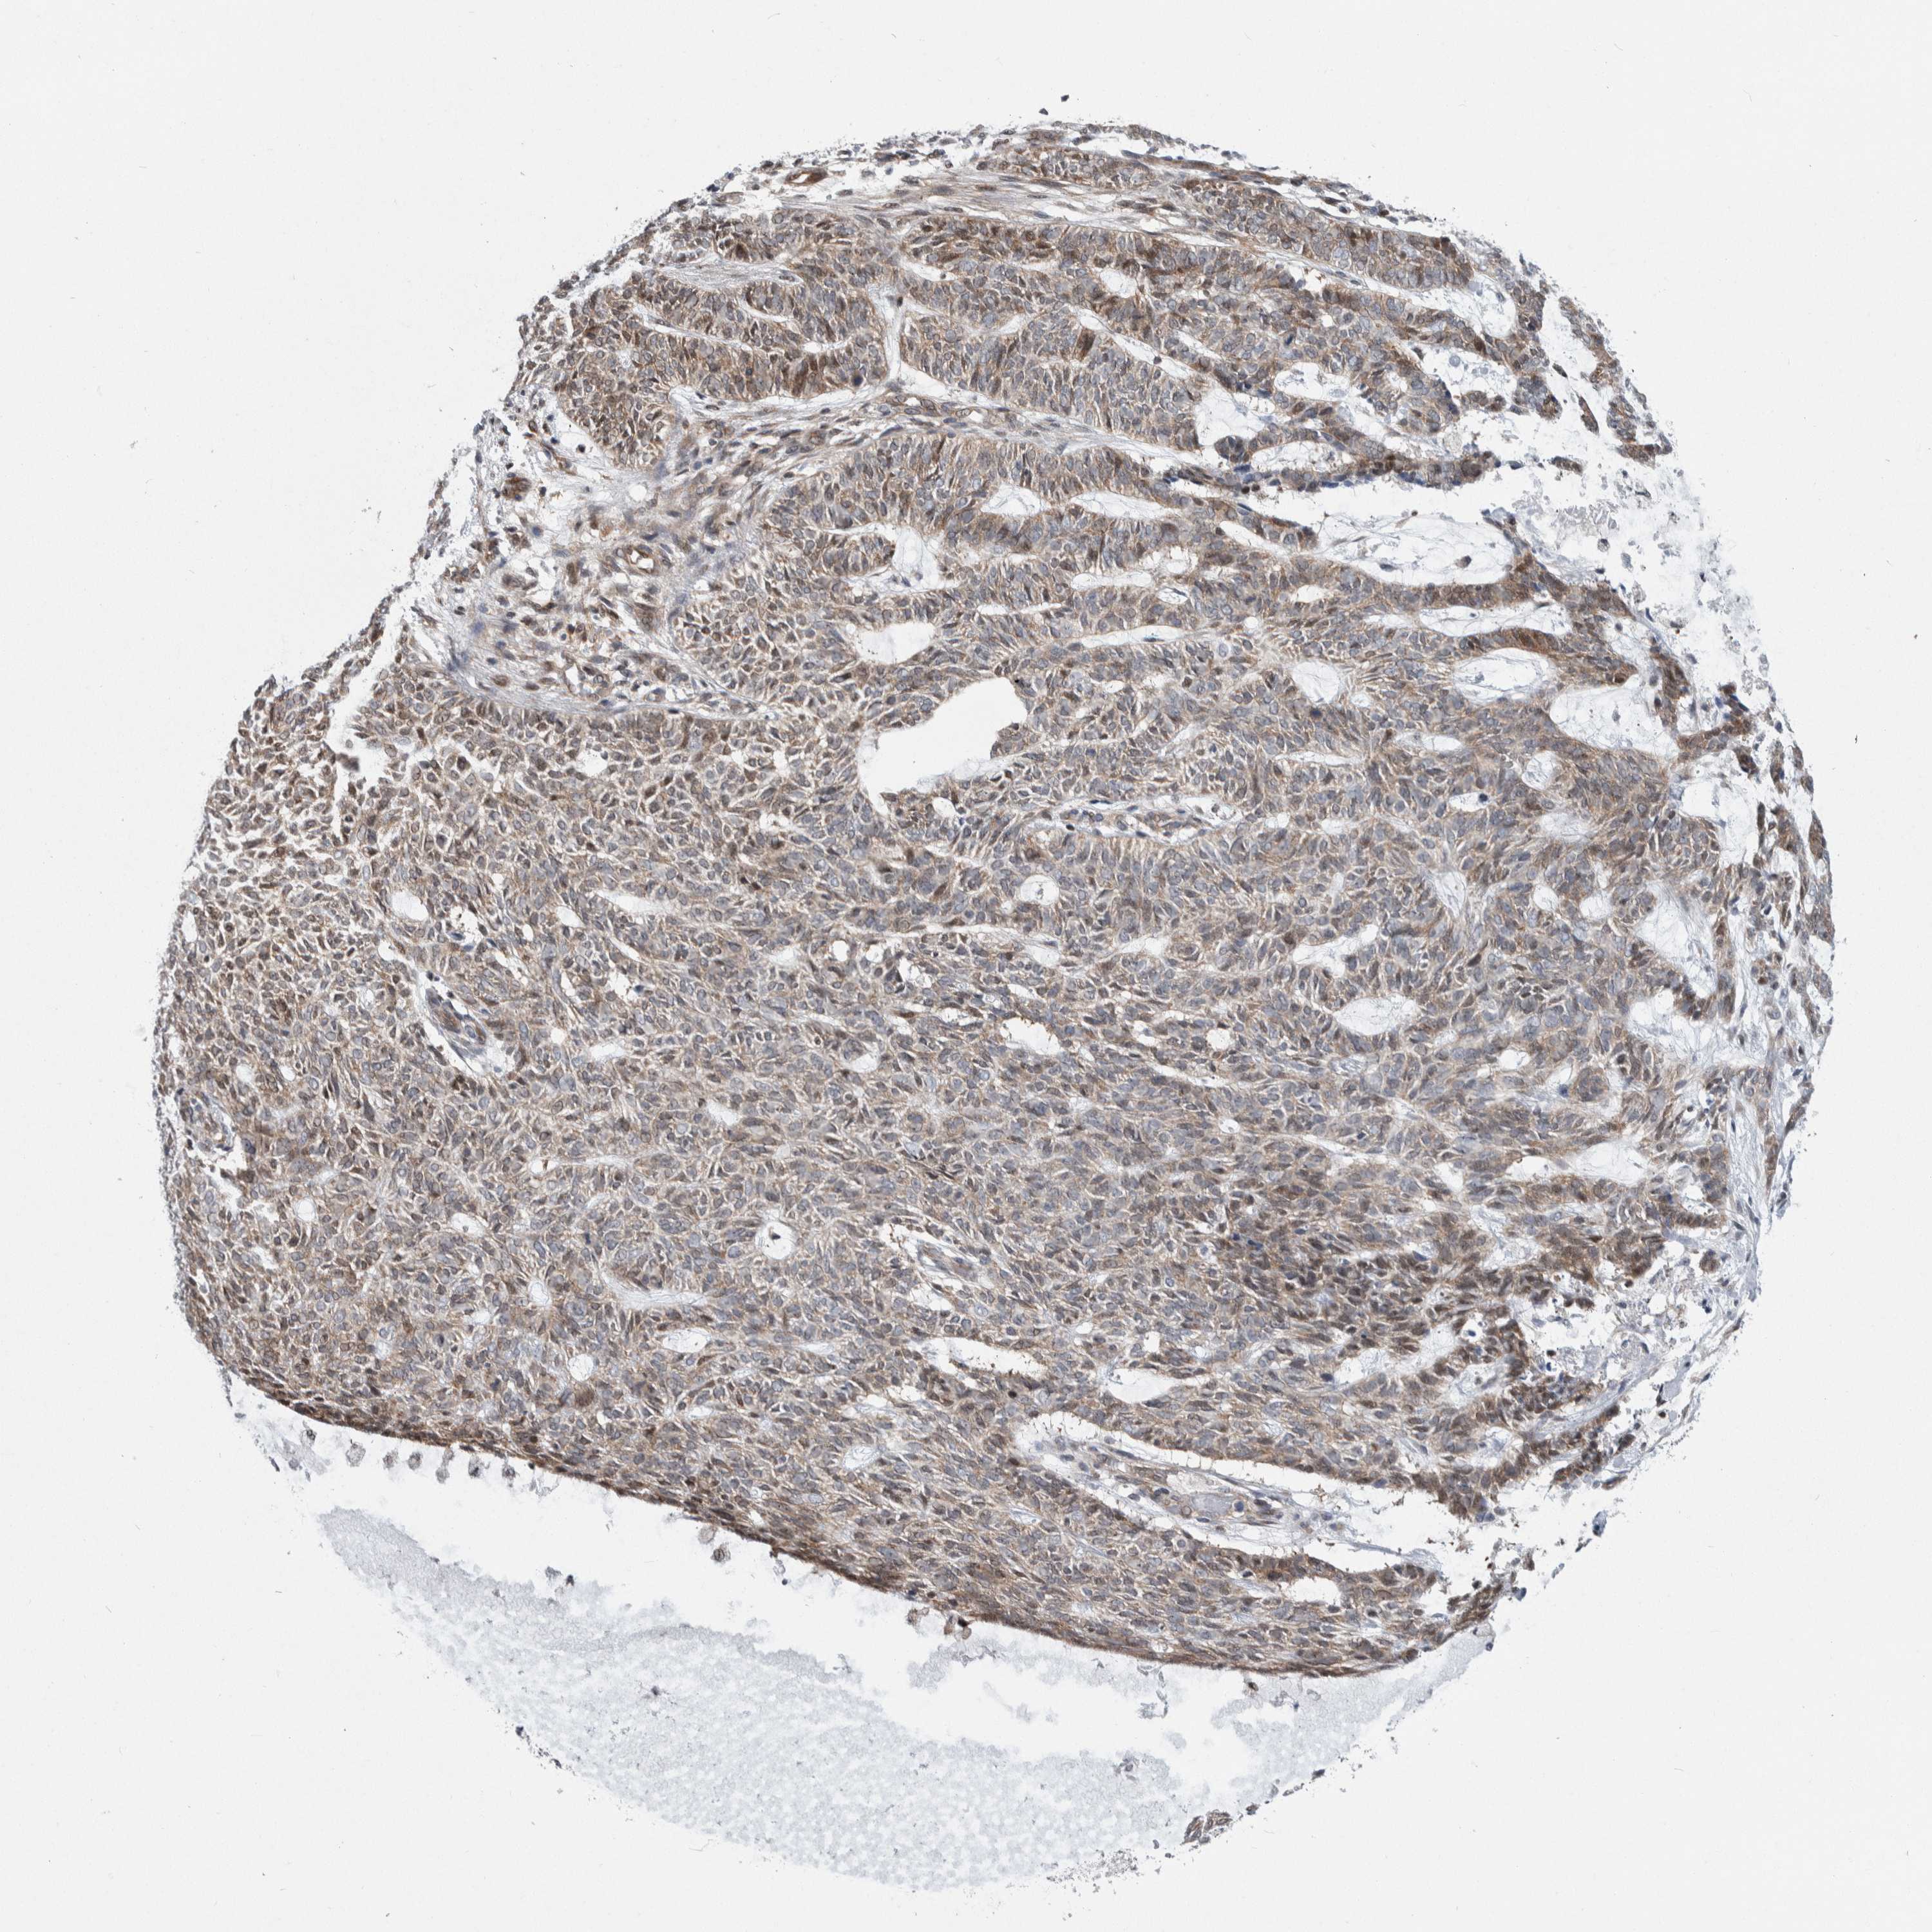

SKIN CANCER - Protein expressioni

A mouse-over function shows sample information and annotation data. Click on an image to view it in a full screen mode. Samples can be filtered based on level of antibody staining by selecting one or several of the following categories: high, medium, low and not detected. The assay and annotation is described here.

Each image is clickable and will lead to virtual microscopy that enables deeper exploration of all samples and also displays staining intensity scores, fraction scores and subcellular localization as well as patient and tissue information for each sample.

CAB080052

Squamous cell carcinoma, metastatic, NOS